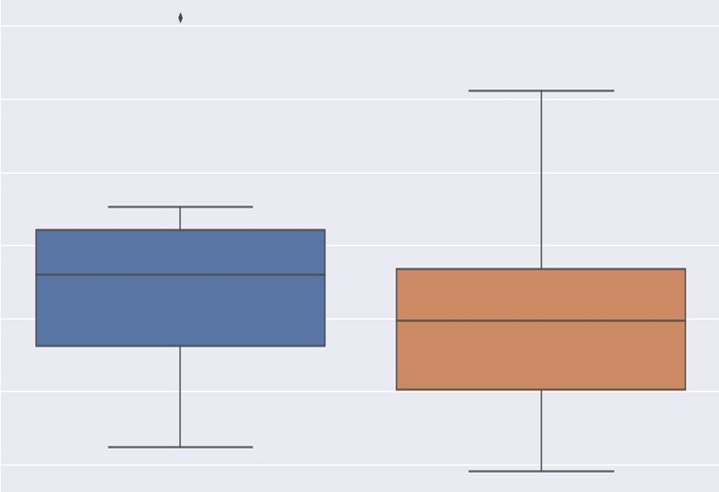

- Care Image Processing

- Healthcare Decision Support

- Healthcare Research